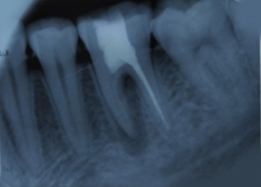

Hemisectomy

Pre-OP IOPAR